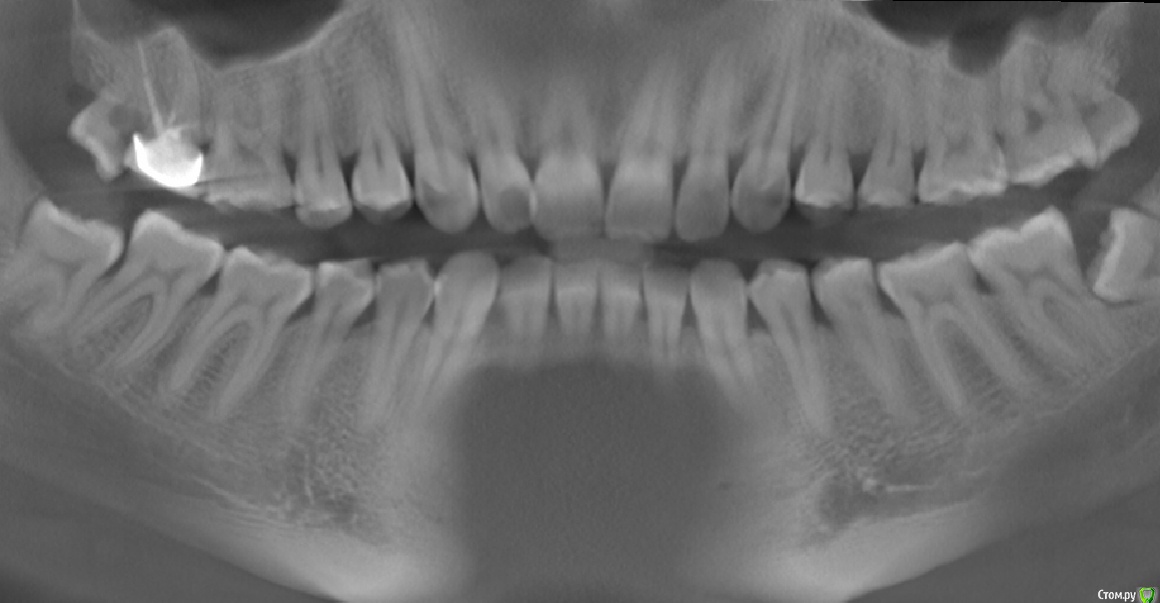

AlexNick Опубликовано 27 ноября, 2015 Поделиться Опубликовано 27 ноября, 2015 Добрый день. Очень нужна консультация по сложной проблеме.Три года назад мне установили коронку на 7-й верхний зуб. После установки коронки я ощущал небольшой дискофорт при смыкании зубов, однако врач проверил прикус и сказал, что всё в норме. Однако уже через месяц я заметил повышенное напряжение жевательных мышц и снова обратился к тому же специалисту. Он ответил, что с коронкой это никак не связано и, скорее всего, "просто стресс".В течение последующих лет напряжение жевательных мышц стало беспокоить всё больше.В этом году напряжение (спазм) распространилось ещё на область висков и стало намного сильнее. После жевания твёрдой пищи стали возникать болевые ощущения в зубах и около ушей, которых проходили только через несколько дней.Также заметил затруднения при открывании рта и щелчки при жевании в суставе.Кроме того, в этом году у меня начал появляться над десной 8-й правый нижний зуб, а на верхних зубах мудрости обнаружили кариес.Ко всему прочему, полгода назад я стал замечать видимую на глаз стираемость зубов и уменьшение межзубных промежутков на нижней челюсти (раньше мог прочищать некоторые из них зубной нитью, а сейчас - нет).Стоматологи в моём городе не занимаются проблемой ВНЧС и гипертонуса жевательных мышц. Просто кто-то рекомендует поскорее удалить все восьмёрки, кто-то рекомендует подождать ввиду травматичности удаления нижних зубов.Я сделал также МРТ ВНСЧ: частичная латеральная дислокация суставного диска правого ВНЧ сустава с полной репозицией. Артроз левого ВНЧ сустава 0-1 ст. МР-признаки функциональной перегрузки латеральных крыловидных мышц.При обследовании в Москве у меня ещё обнаружили глубокий прикус и рекомендовали ортодонтическое лечение.У меня возник следующий вопрос: с чего начинать лечение - с удаления зубов мудрости (но это будет тяжело в силу проблем с суставом и мышцами и может усугубить проблему?) или с коррекции состояния жевательных мышц и ВНЧ сустава (например, ботулинотерапия)? Ссылка на комментарий